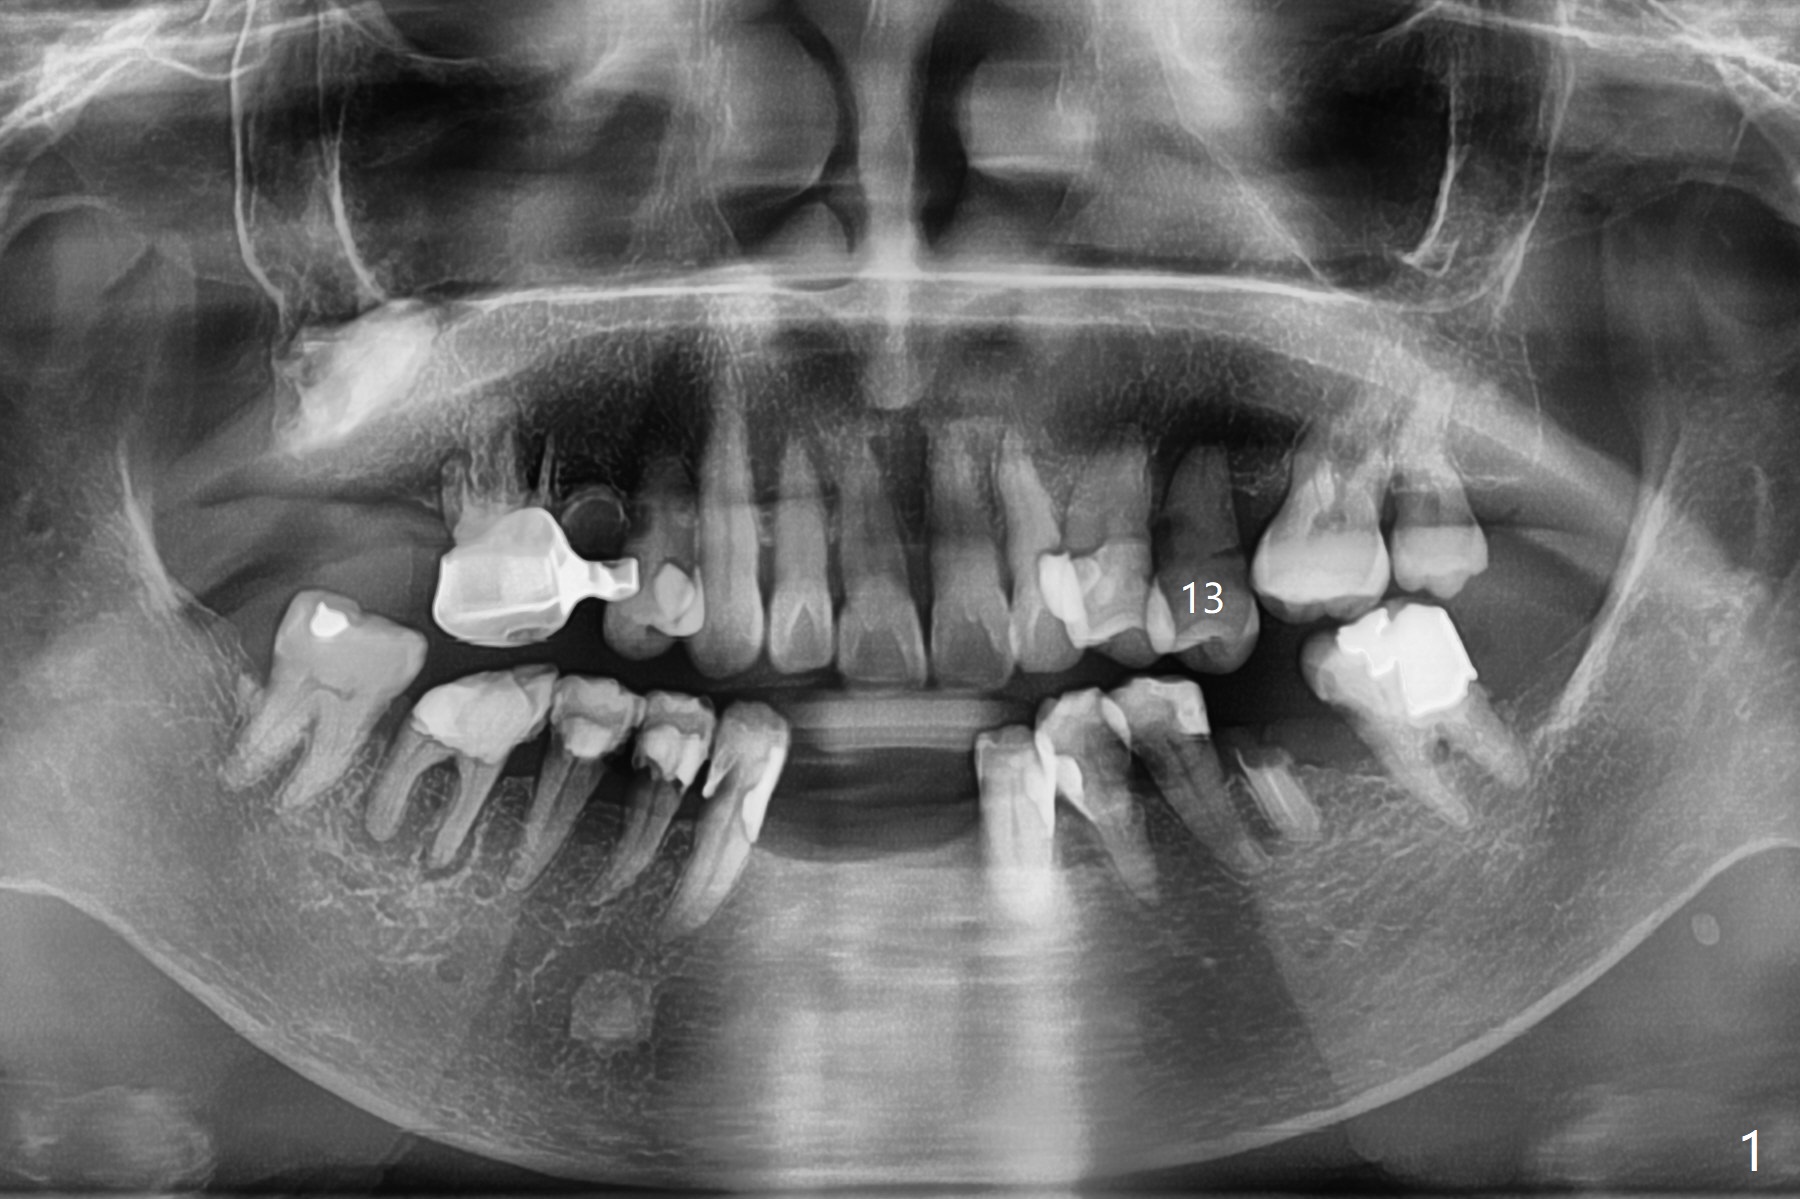

A 82-year-old woman without history of osteoporosis (regular exercises) has poor dentition (Fig.1). Her concern is a loose tooth at #13 (Fig.2). The bone available for implantation seems to be unlimited (Fig.3, taken 3 years earlier). The longest implant will be used to compensate for low bone density, if there is no osteoporosis. Since the bone loss is severe, a bone-level implant provides flexibility in choosing an abutment with various length of the cuff (including mill abutment).